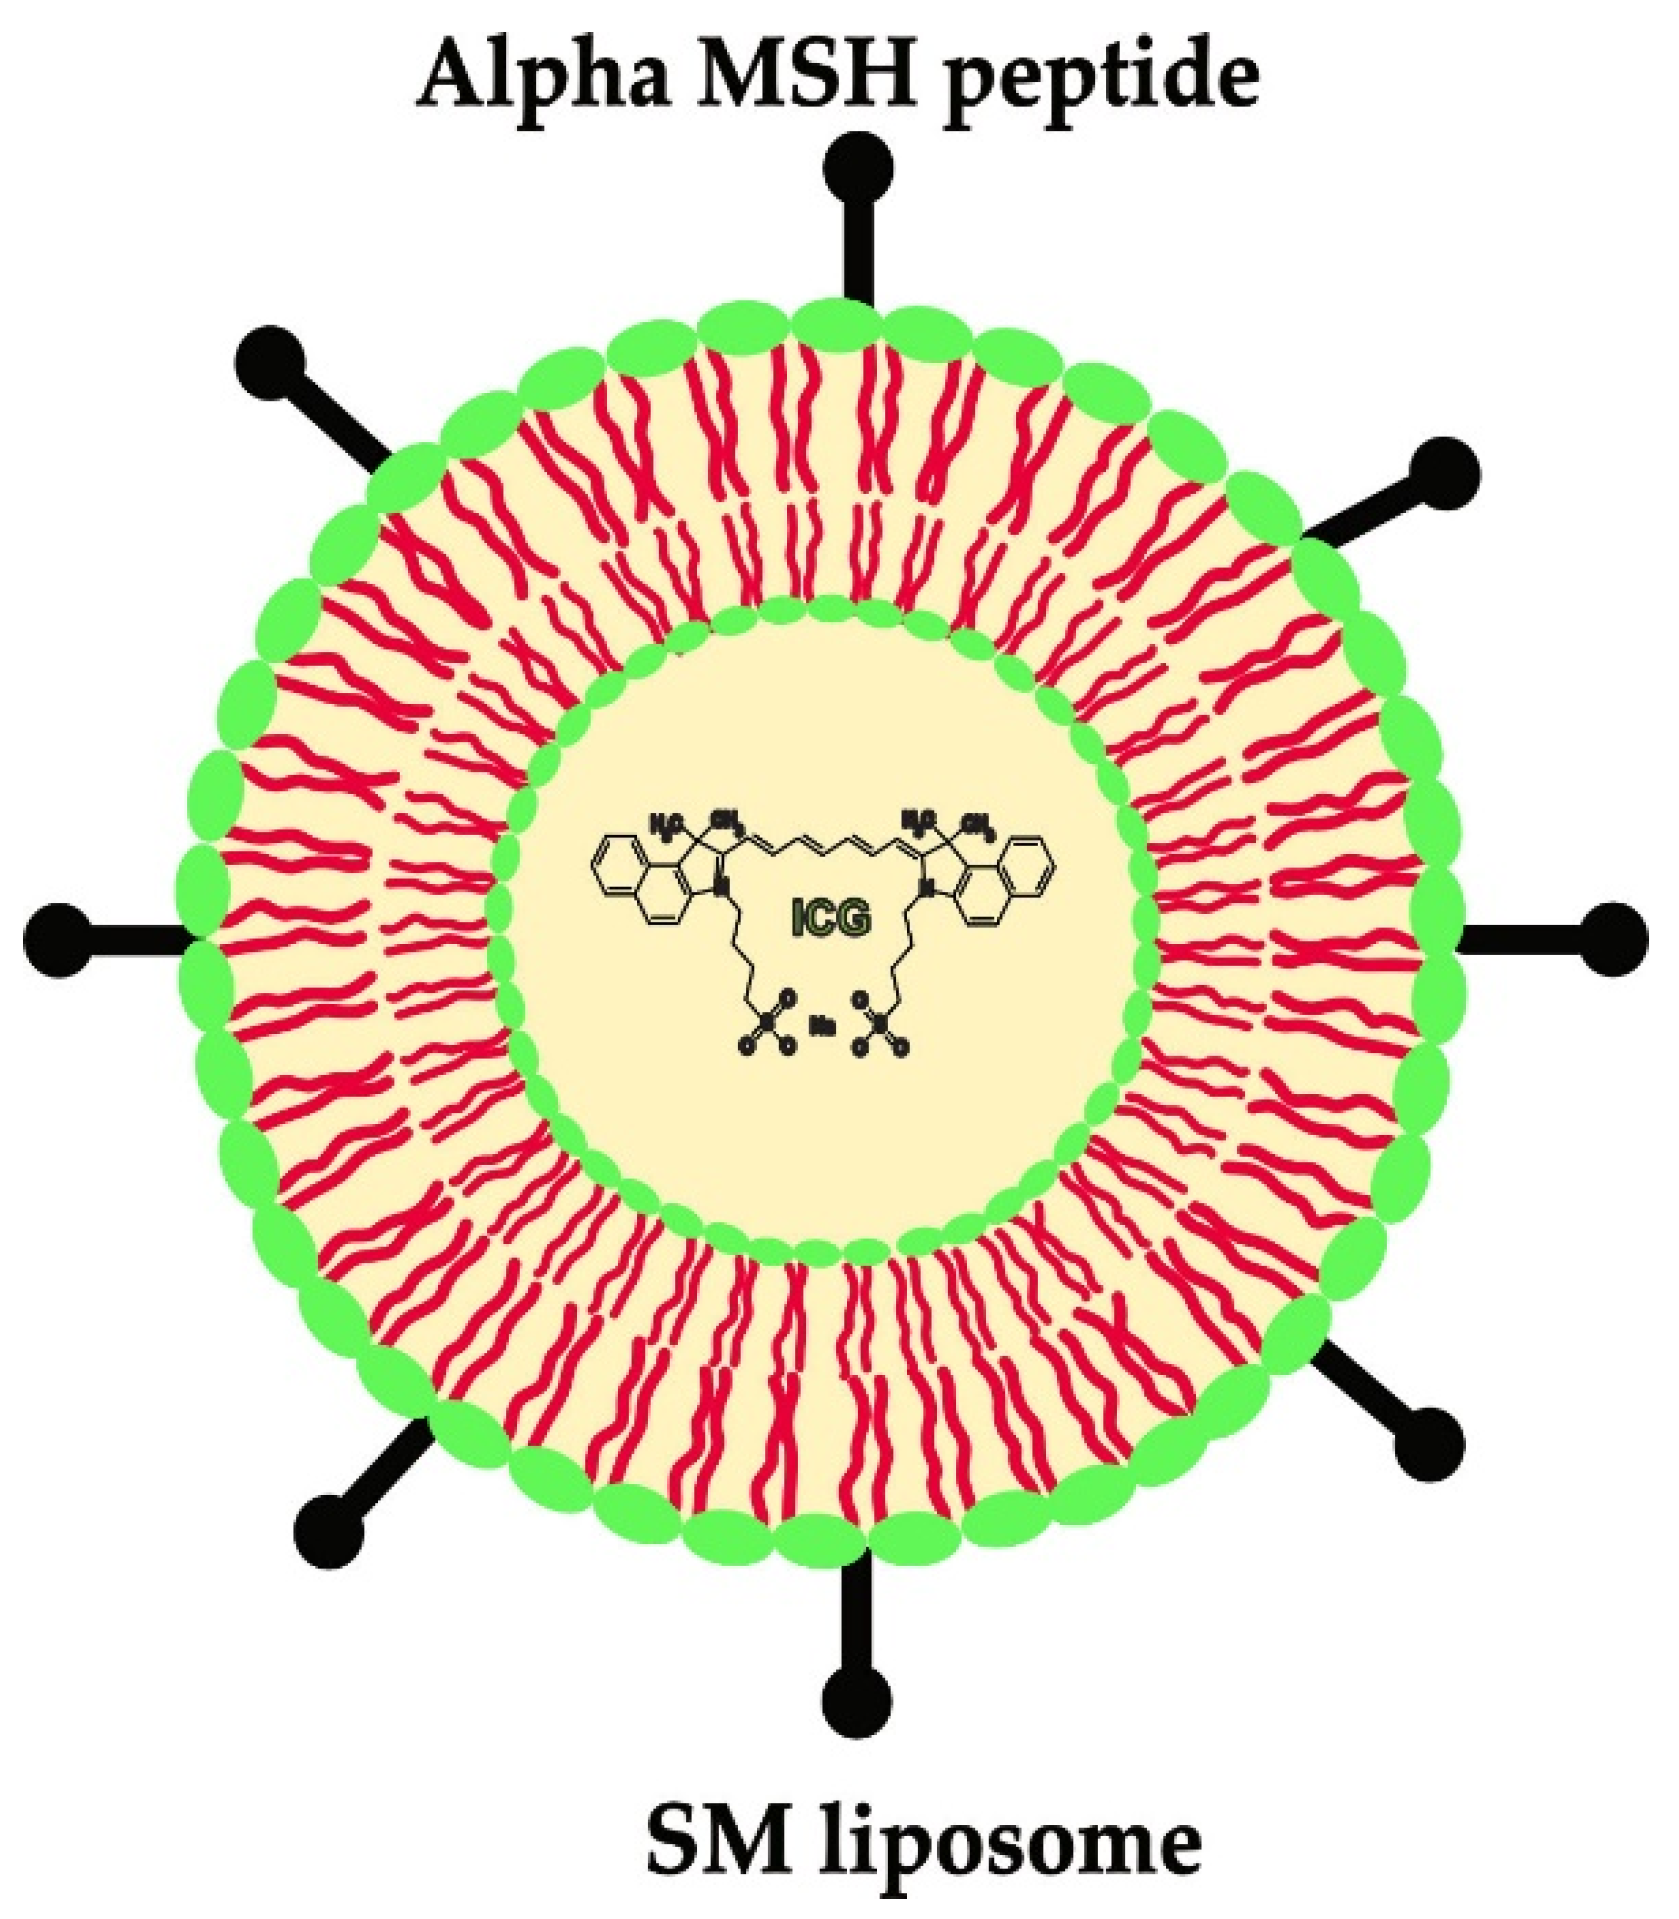

2.1. In Vitro Assay for α-MSH-SM-Liposome and Mg and/or Mg-10Gd Interaction

4.2. Preparation of α-MSH-SM-Liposome

4.3. In Vitro Studies: Material and Liposome Effect on Each Other